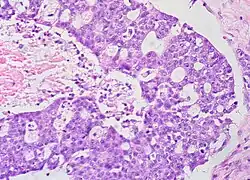

| Micrograph of a mucinous ovarian carcinoma stained by H&E | |

Mucinous tumors include mucinous adenocarcinoma and mucinous cystadenocarcinoma.[29]

Mucinous adenocarcinoma

Mucinous adenocarcinomas make up 5–10% of epithelial ovarian cancers. Histologically, they are similar to intestinal or cervical adenocarcinomas and are often actually metastases of appendiceal or colon cancers. Advanced mucinous adenocarcinomas have a poor prognosis, generally worse than serous tumors, and are often resistant to platinum chemotherapy, though they are rare.[29]